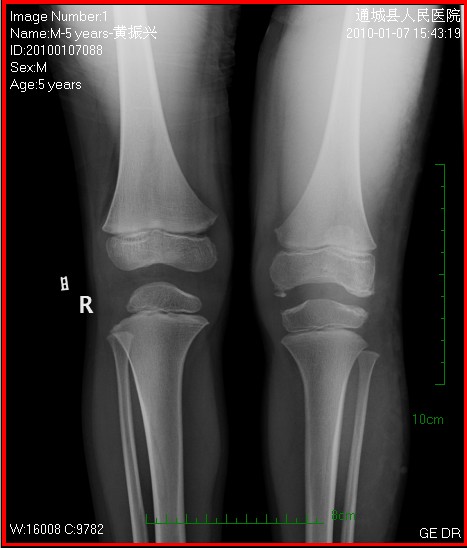

以下是引用学者~『风』在2010-1-8 21:17:00的发言:[br]先天性髌骨发育不全,骨质轻度增生

以下是引用随光逐影在2010-1-9 8:21:00的发言:[br]考虑左侧大、小腿外侧软组织内蔓状血管瘤伴左膝关节侵蚀,左侧髌骨及左侧股骨下端、胫骨上端骨骺异常发育。

以下是引用zxl51642在2010-1-9 17:29:00的发言:[br]首先要排除外敷药物等伪影,软组织血管瘤彩超没看见?[br]关节面凸凹不平,软骨及软骨下骨坏死,股骨内髁下方见碎骨片影,可能:1、首先考虑幼年型类风湿;2、股骨髁缺血性坏死,原因可能类似blount';s病机理;3、男性患儿查个尿排除尿黑酸症。